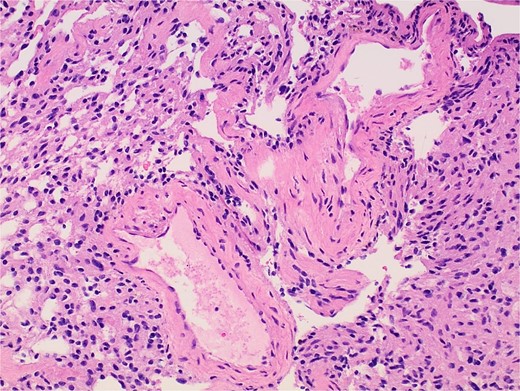

Gross examination and cut sections revealed fragments of tan–white to tan–yellow tissue with some areas of hemorrhage measuring from 1.1 to 3.6 cm in the greatest dimension. Histopathological examination of the excised mass confirmed the diagnosis of a retroperitoneal schwannoma, characterized by S100 positivity (Fig. 3) and degenerative changes, including hemorrhage, hemosiderin, and cystic degeneration (Fig. 4), nuclear atypia (Fig. 5), and perivascular hyalinization (Fig. 6).

Photomicrograph of diagnostic histopathology showing cystic degeneration and hemorrhage with hemosiderin laden macrophages.